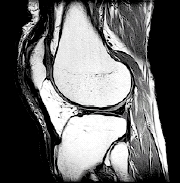

RESONANCIA MAGNÉTICA. Se trata de una prueba detallada de diagnóstico por imágenes en la que se pueden observar los huesos, cartílagos, ligamentos y otros problemas musculares sin usar rayos X.

| Las pruebas de diagnóstico por imágenes, tales como la resonancia magnética, ayudan al proveedor de atención médica a determinar la causa de su problema de rodilla. |